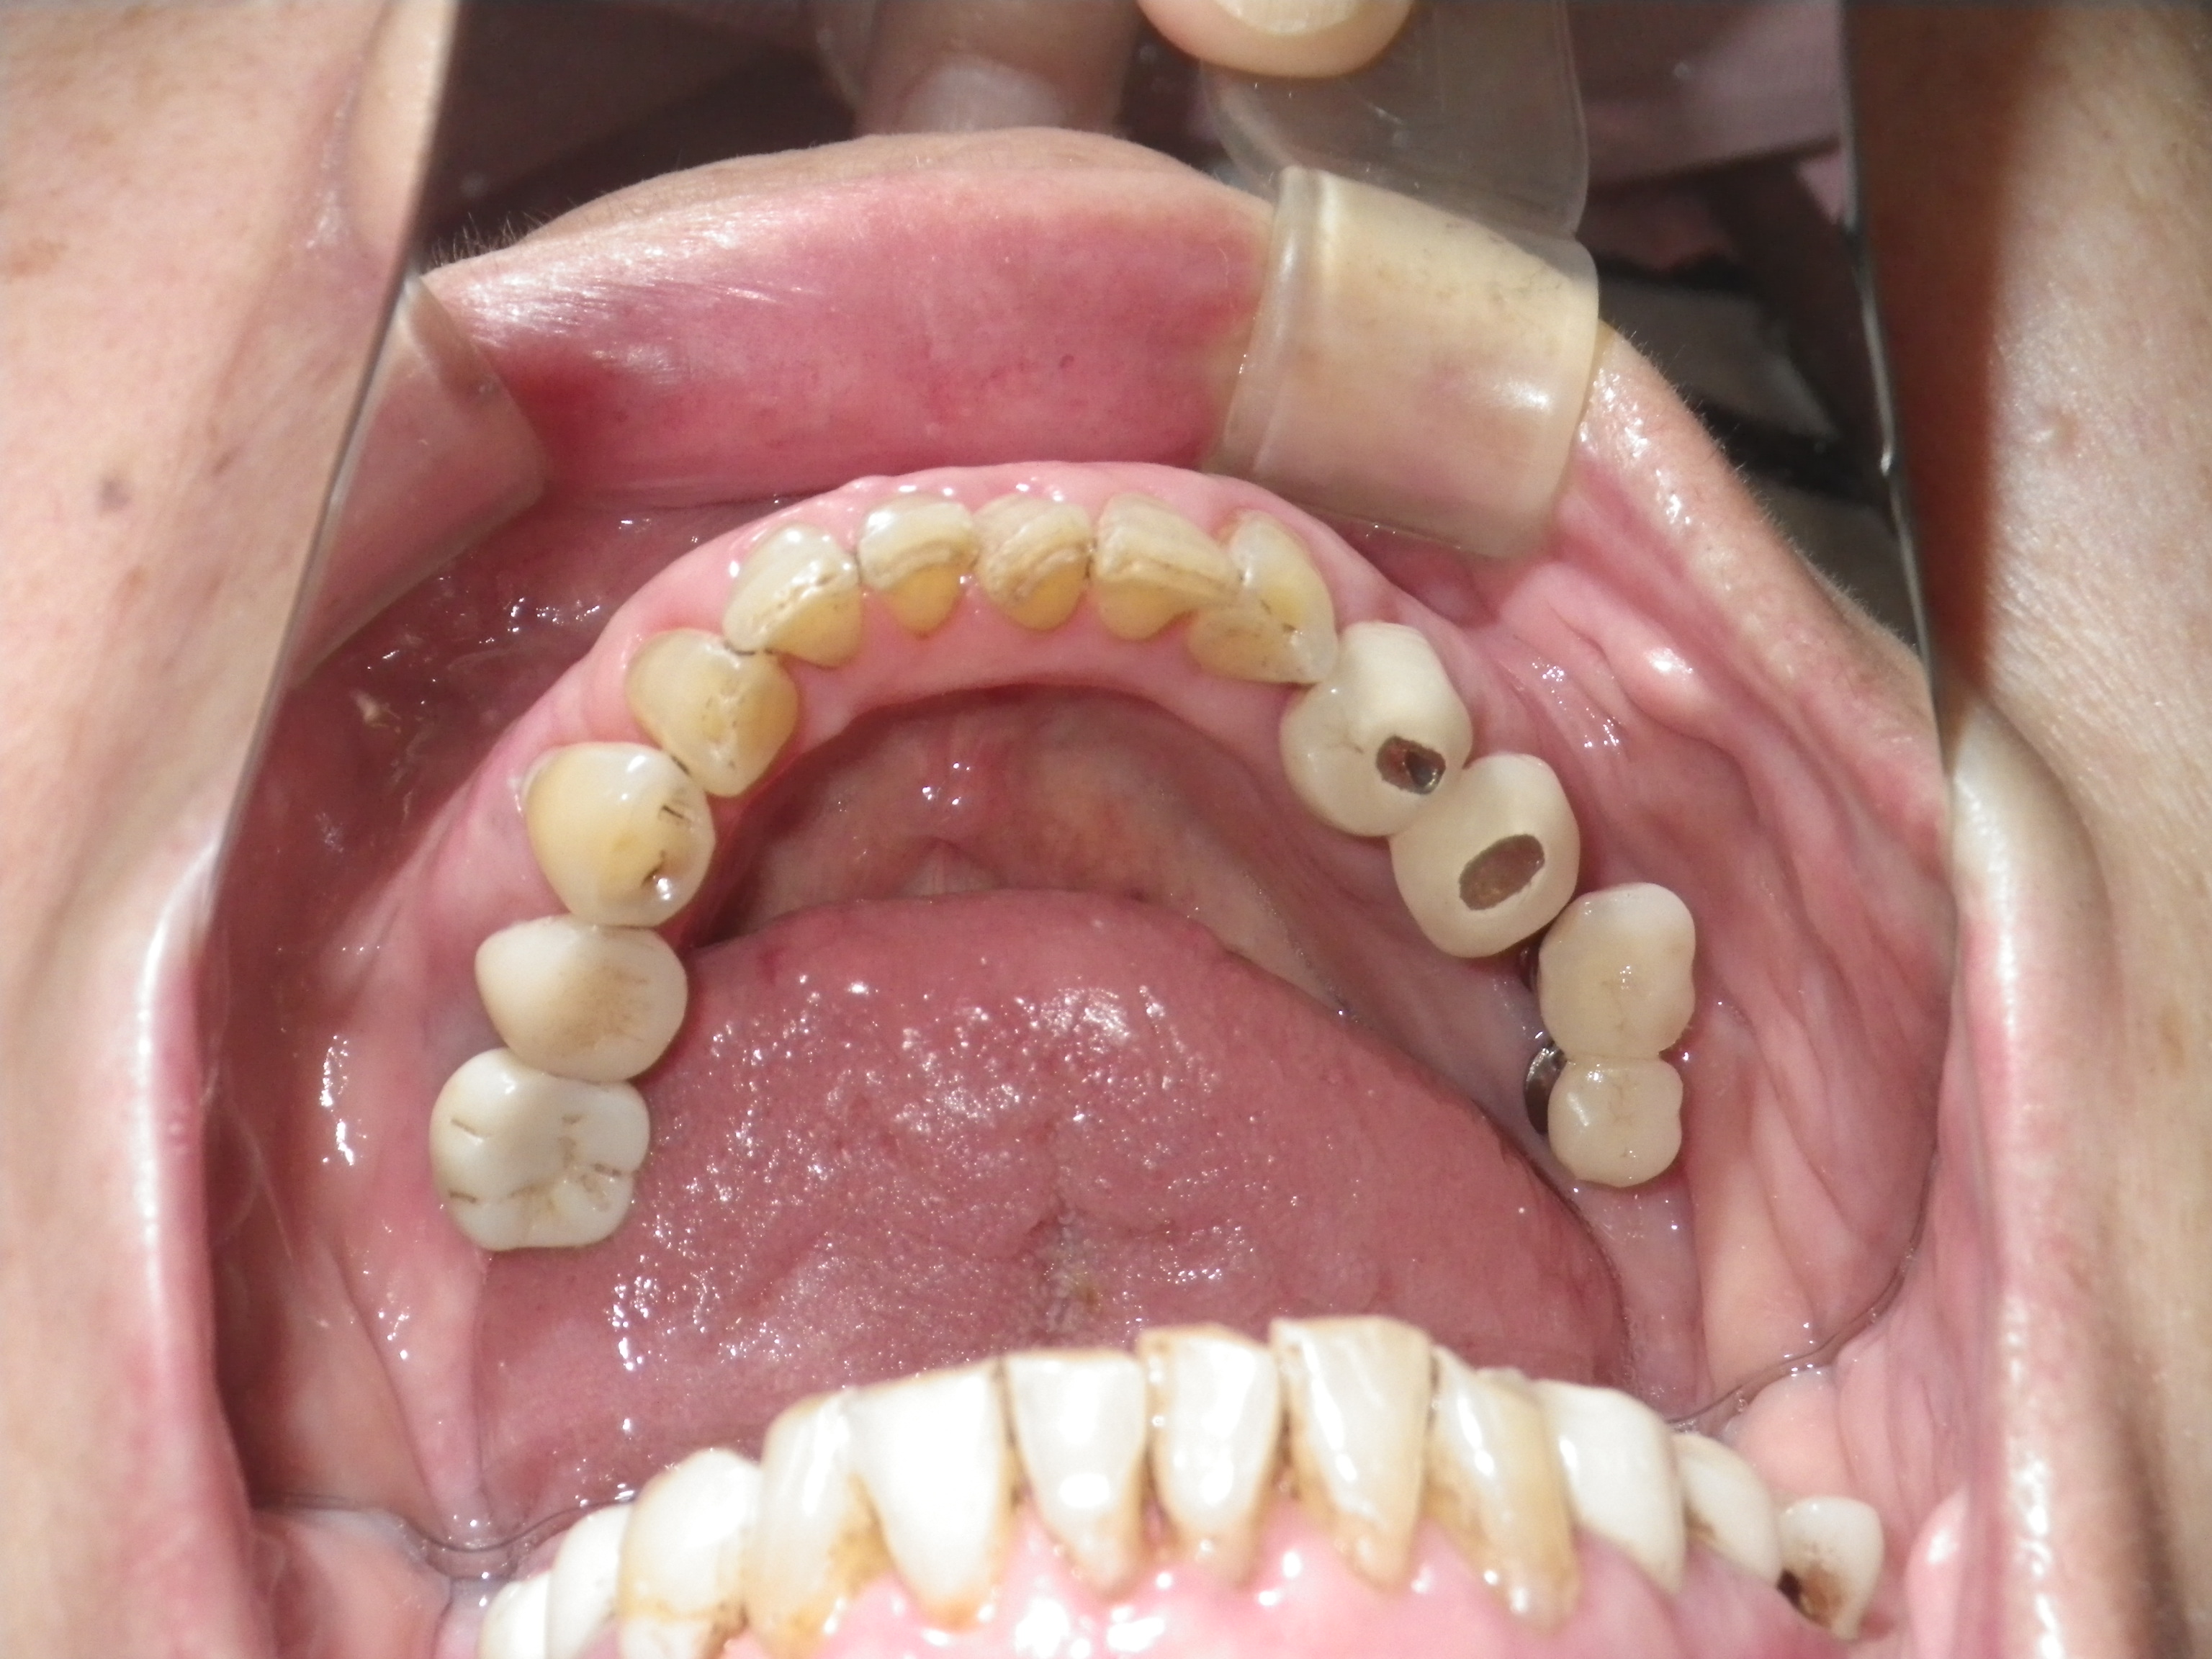

重度歯周病患者にインプラント治療(続き)

インプラント、重度歯周、サイナスリフト、ネジ山

重度歯周病患者にインプラント治療

重度歯周病

骨が足りない